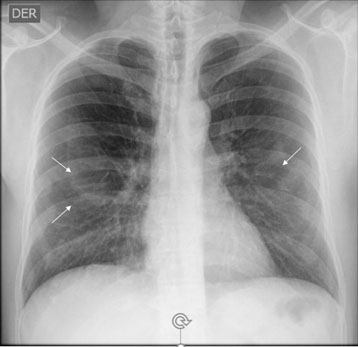

Frente a la presencia de alteraciones pleurales en la Radiografía de tórax con técnica OIT y confirmadas con tomografía computarizada de tórax de alta resolución sin contraste (TCAR), será de vital importancia realizar el diagnóstico diferencial sobre alteraciones pleurales asociadas a la exposición al amianto (Figuras 2, 3, 4 y 5). Entre las patologías diferenciales se incluyen: 53

Radiografía de tórax con técnica OIT: La radiografía de tórax con técnica OIT es una herramienta inicial para evaluar las alteraciones pleurales. Puede revelar la presencia de derrame pleural, engrosamiento o calcificaciones pleurales (Figura 3).

Complementaria: Tomografía computadorizada de tórax de alta resolución. 36 (TCAR), sin contraste: en caso de lectura de radiografía de tórax con técnica OIT que muestre opacidades irregulares de predominio, en bases pulmonares con profusión 1/0 y 1/1. Además, es una herramienta fundamental para la realización de diagnóstico diferencial (Figura 2).